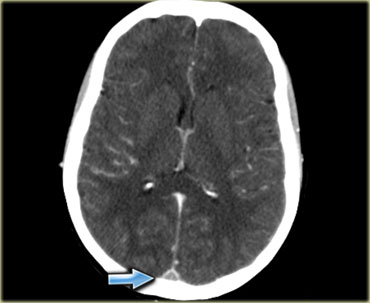

Dấu hiệu cục máu đông tăng tỷ trọng (2)

Hình ảnh tĩnh mạch vỏ não bị huyết khối biểu hiện dưới dạng một dải hoặc đường tăng tỷ trọng hình dây thừng còn được gọi là dấu hiệu dây thừng (cord sign).

Một thuật ngữ khác thường được sử dụng là dấu hiệu mạch máu tăng tỷ trọng (dense vessel sign).

Dấu hiệu cục máu đông tăng tỷ trọng (3)

Hình ảnh bên trái là của một bệnh nhân có nhồi máu xuất huyết ở thùy thái dương (mũi tên đỏ).

Lưu ý xoang ngang tăng tỷ trọng do huyết khối (mũi tên xanh dương).